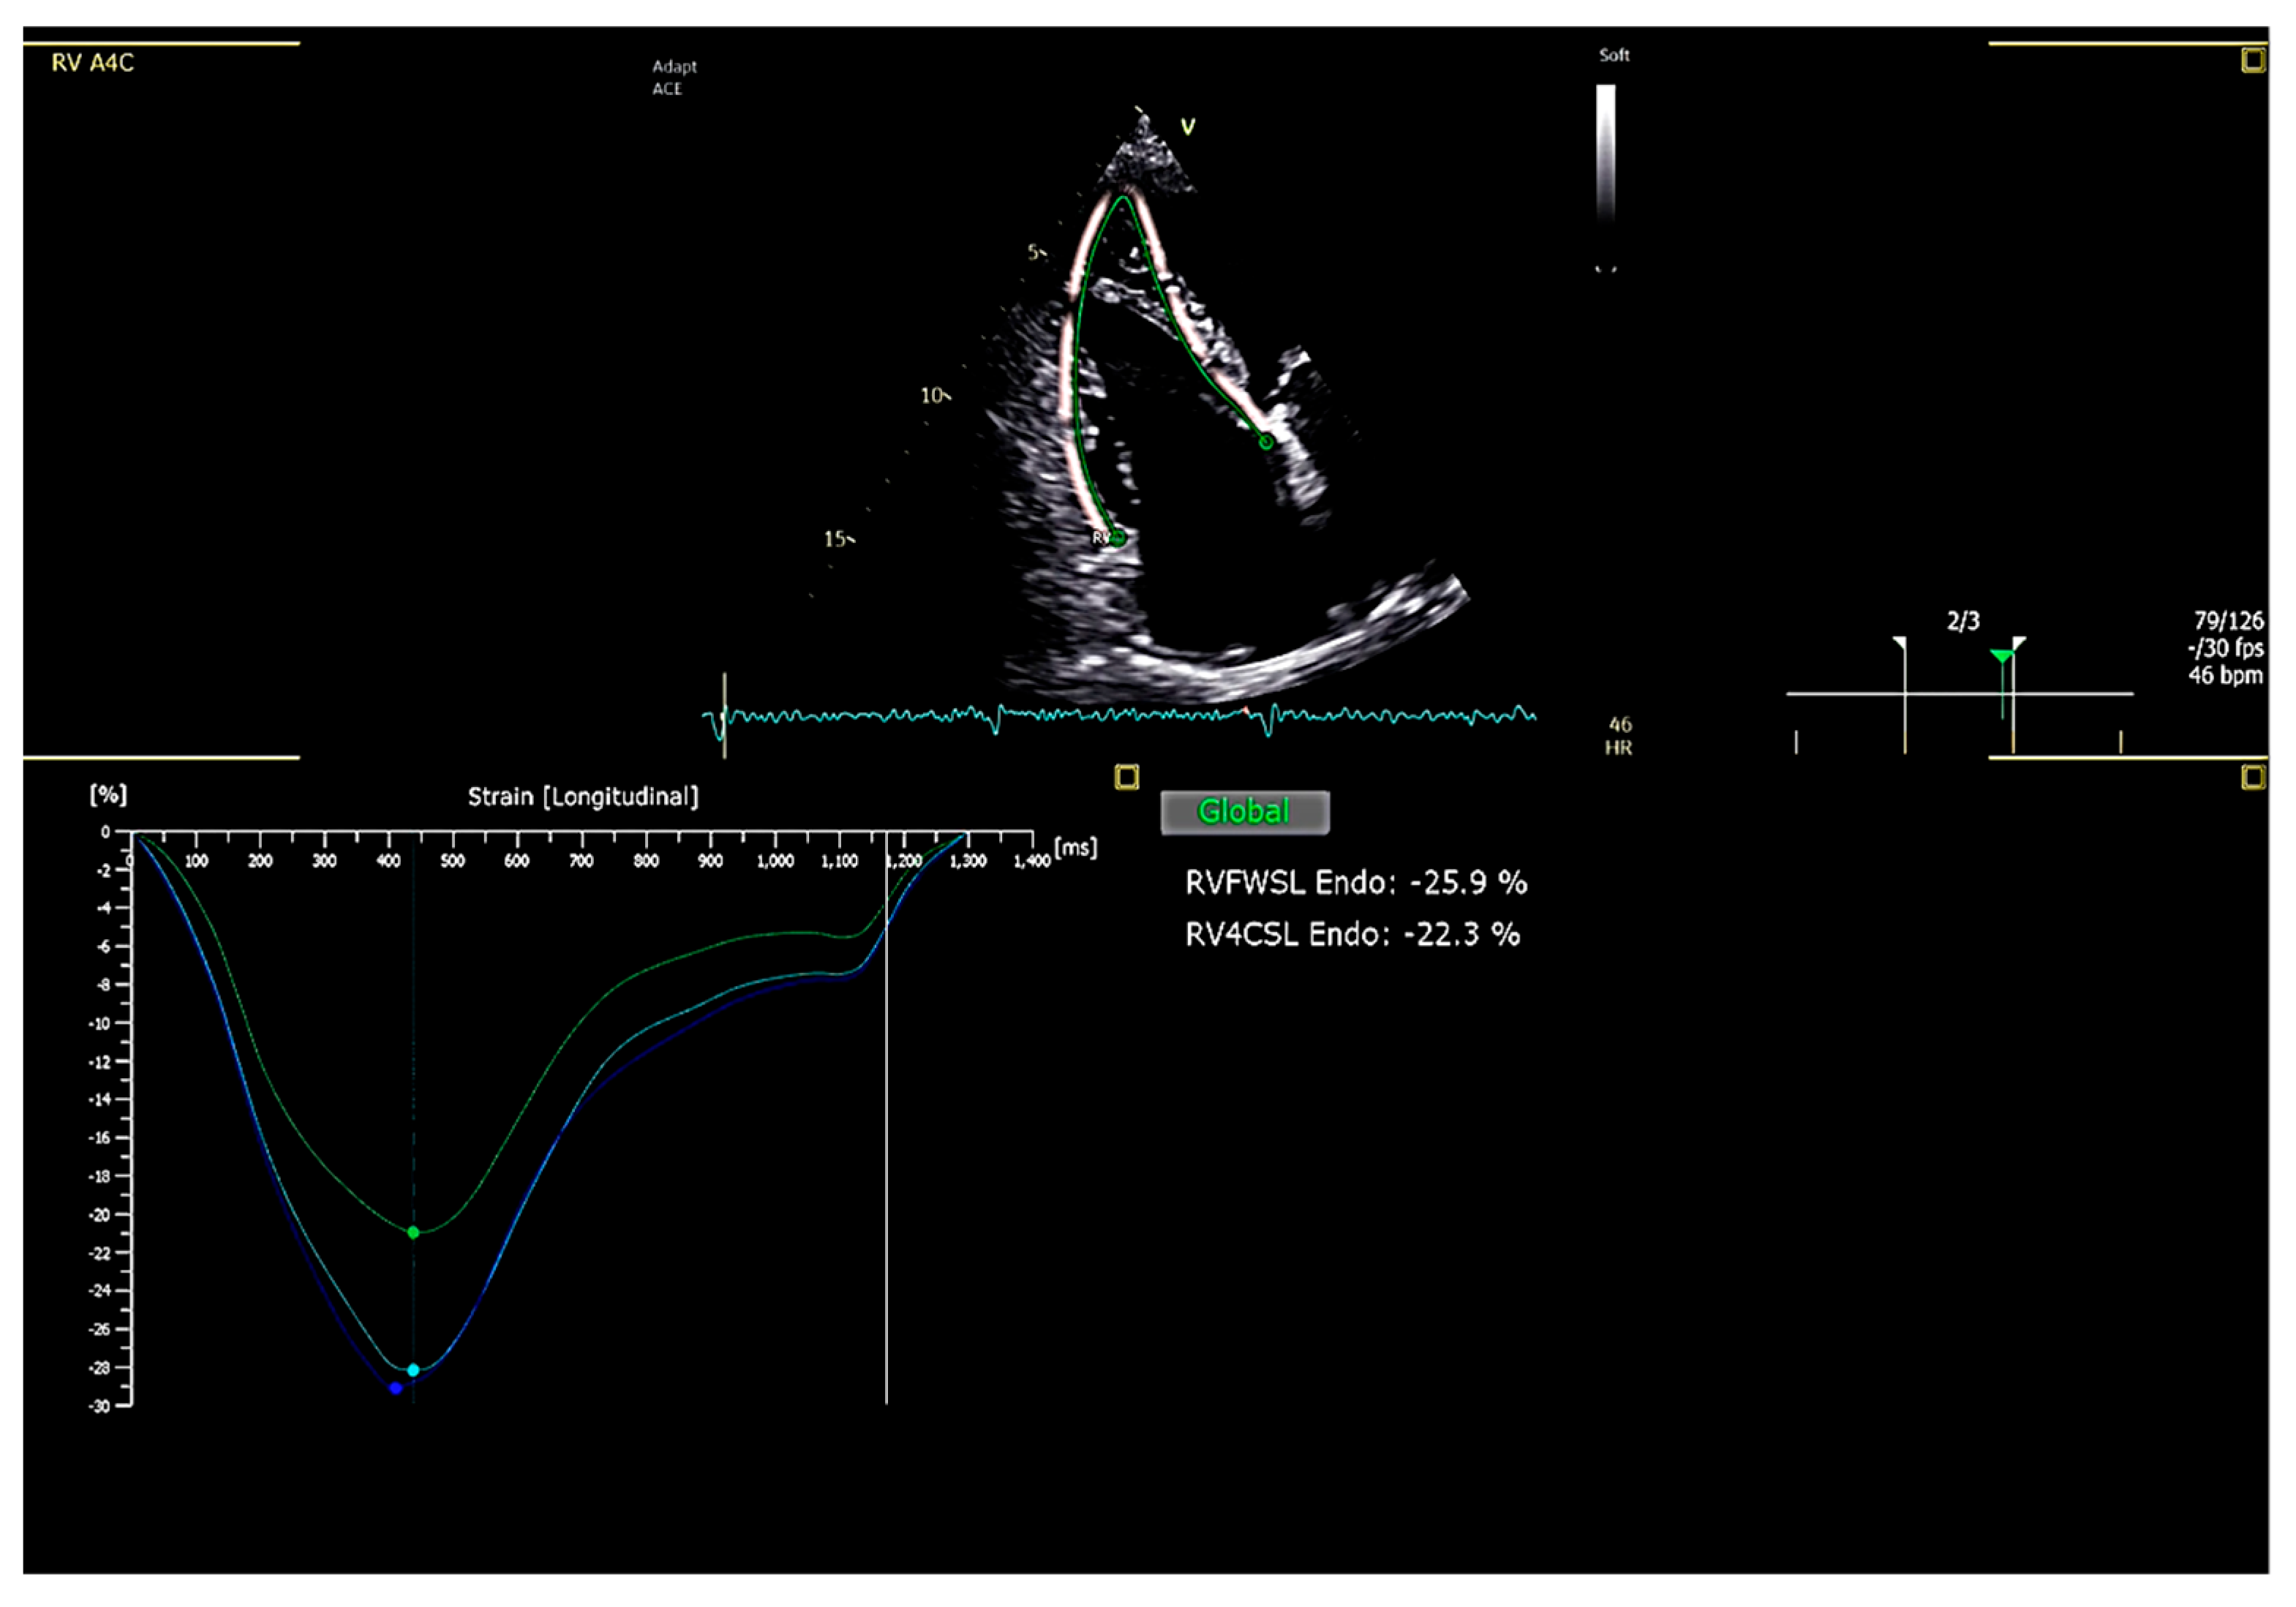

5. Right Ventricular Free Wall Longitudinal Strain (RVFWLS)